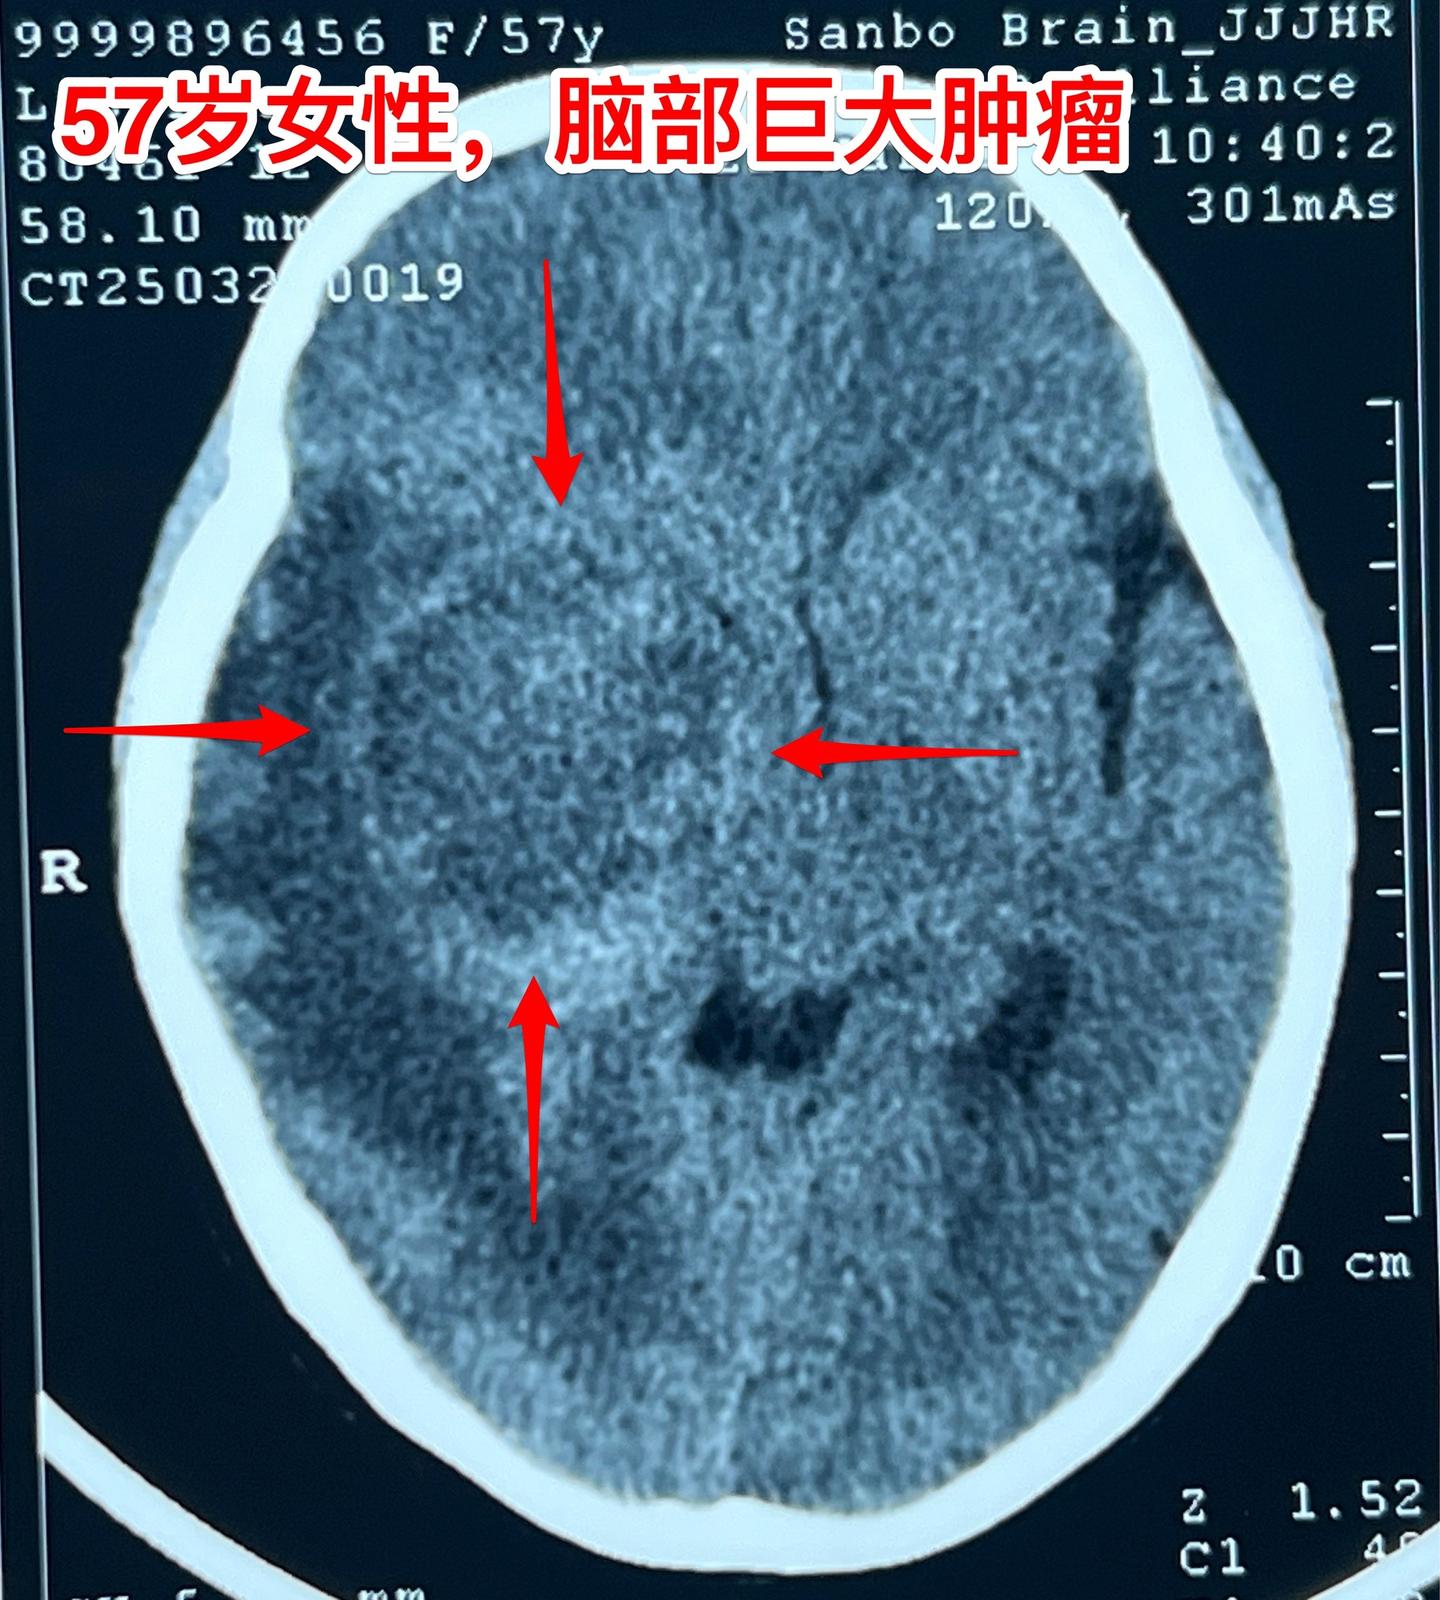

肺癌患者多年后出现脑部转移。57岁的韶关女病人在18年前患肺癌,作了手术切除肺癌并作了化疗,随后多次复查,没有发现肿瘤复发。她也在正常上班。 就在这个春节前她的婆婆去世了,她的情绪似乎受到严重影响,和平时不一样,总是担惊受怕。 三月份经家人提醒,到当地医院去作头部CT检查,结果发现脑部有个瘤,像鸡蛋那么大了!医生怀疑是胶质瘤。 3月22日到北京来找我住院。3月27日晚作了手术,手术中看见肿瘤形态符合肺癌脑转移。等待病理报告。